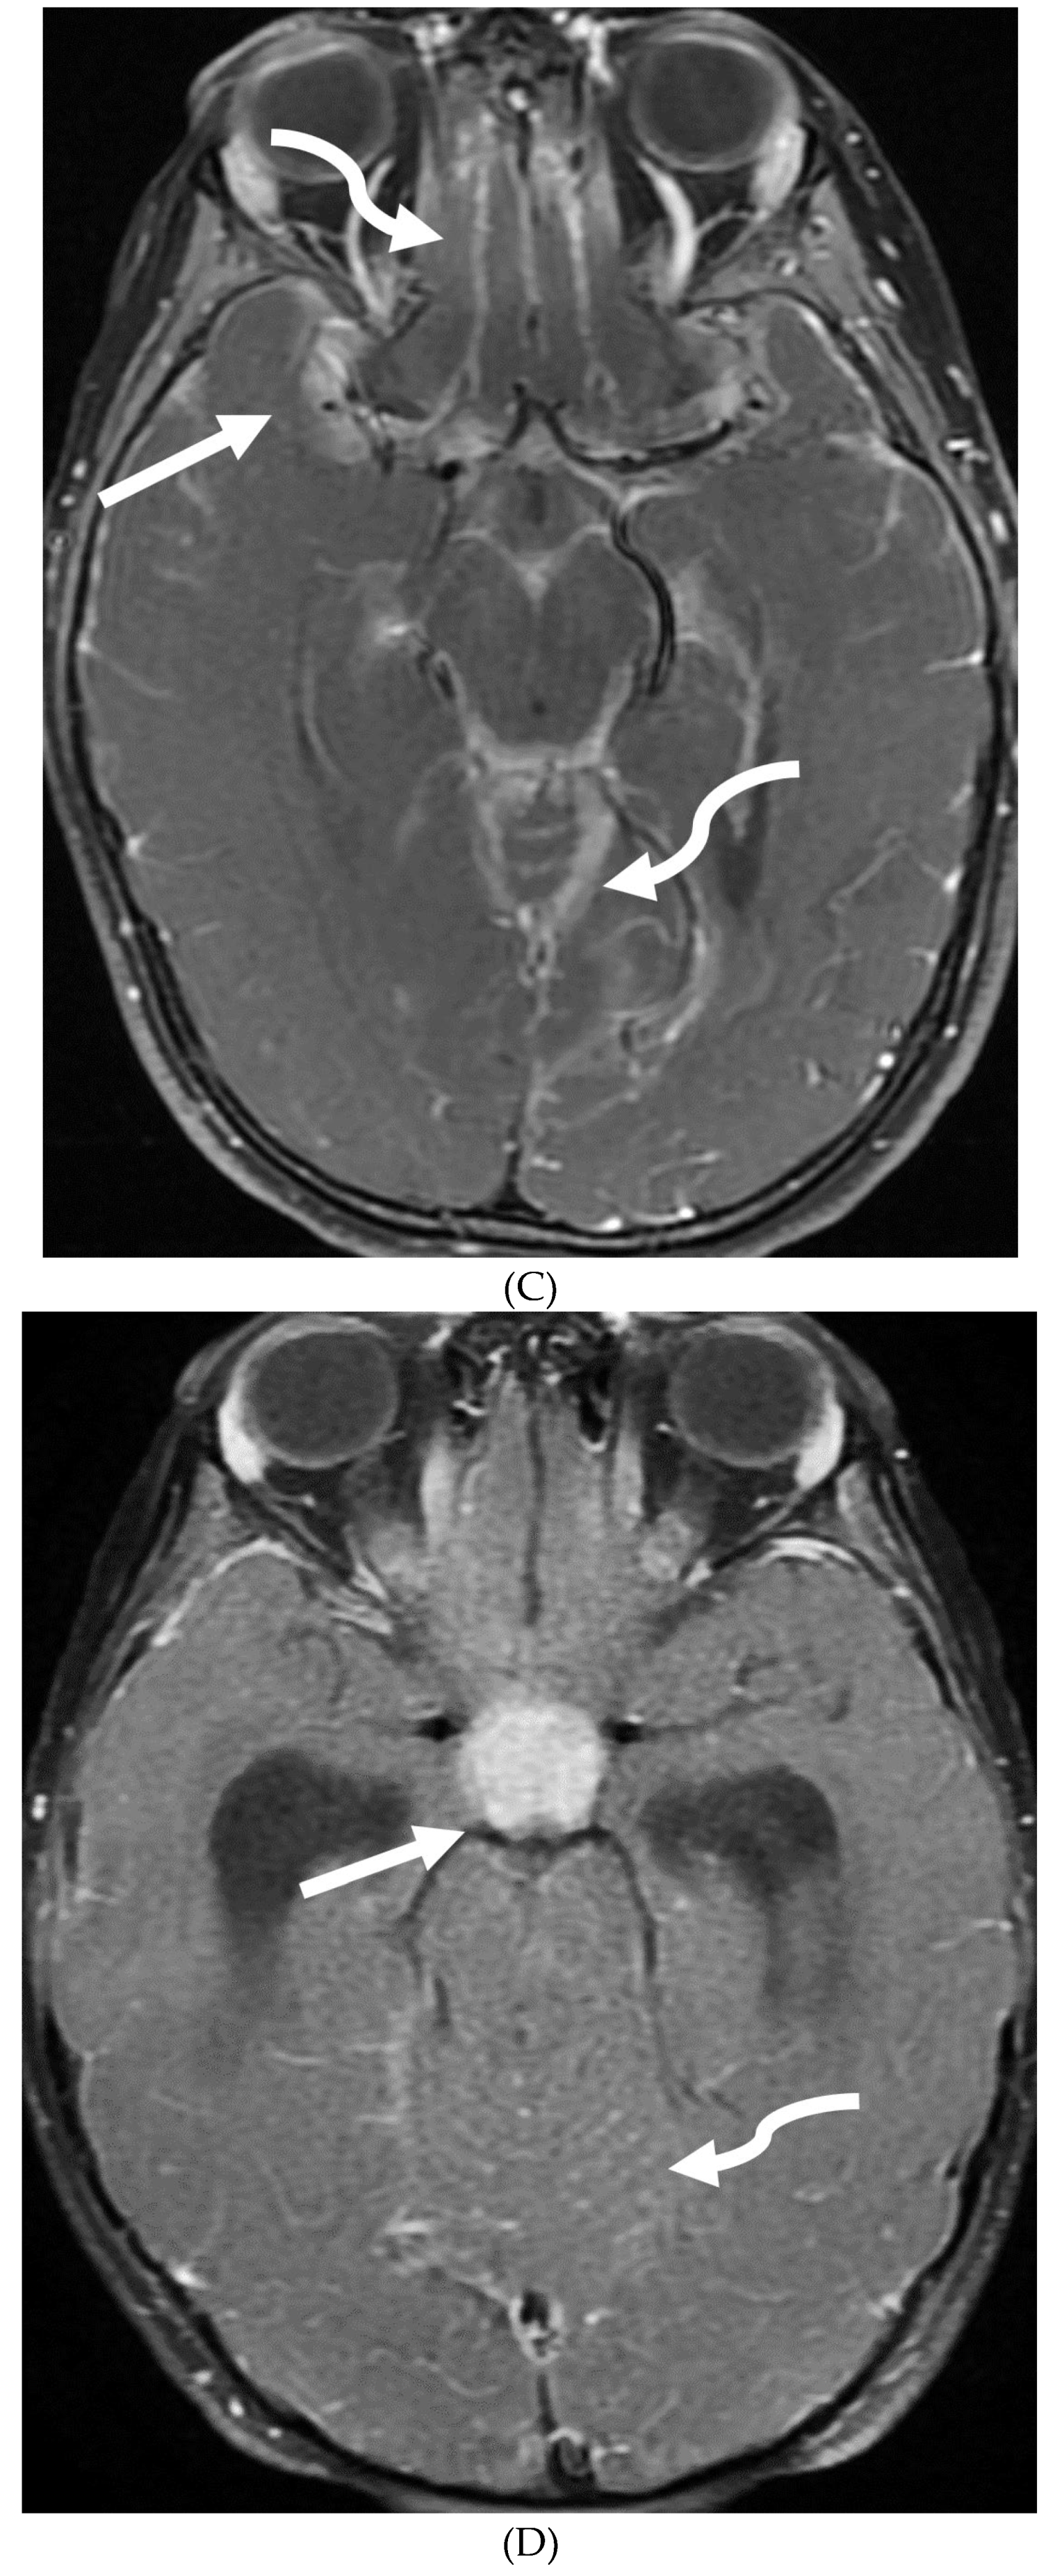

- Horie N, Morikawa M, Nozaki A, Hayashi K, Suyama K, Nagata I. "Brush Sign" on susceptibility-weighted MR imaging indicates the severity of moyamoya disease. AJNR Am J Neuroradiol. 2011 Oct;32(9):1697-702. Epub 2011 Jul 28. PMID: 21799039; PMCID: PMC7965393. [CrossRef]

- Ohta T, Tanaka H, Kuroiwa T. Diffuse leptomeningeal enhancement, "ivy sign," in magnetic resonance images of moyamoya disease in childhood: case report. Neurosurgery. 1995 Nov;37(5):1009-12. PMID: 8559324. [CrossRef]

- Maeda M, Tsuchida C. "Ivy sign" on fluid-attenuated inversion-recovery images in childhood moyamoya disease. AJNR Am J Neuroradiol. 1999 Nov-Dec;20(10):1836-8. PMID: 10588105; PMCID: PMC7657767.